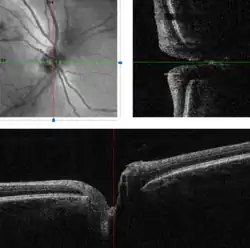

Imaging

Traditional colour-film camera images are the reference standard in imaging, requiring an expert ophthalmic photographer, ophthalmic technician, optometrist or ophthalmologist for taking standardised pictures of the optic disc. Stereoscopic images offer an excellent investigative tool for serial follow-up of suspected changes in the hands of an expert optometrist or ophthalmologist.

Automated techniques have also been developed to allow for more efficient and less expensive imaging. Heidelberg retinal tomography (HRT), scanning laser polarimetry and optical coherence tomography are computerised techniques for imaging various structures of the eyes, including the optic disc. They quantify the nerve fiber layer of the disc and surrounding retina and statistically correlate the findings with a database of previously screened population of normals. They are useful for baseline and serial follow-up to monitor minute changes in optic disc morphology. Imaging will not provide conclusive evidence for clinical diagnosis however, and the evidence needs to be supplanted by serial physiological testing for functional changes. Such tests may include visual field charting and final clinical interpretation of the complete eye examination by an eye care physician. Ophthalmologists and optometrists are able to provide this service.

A systematic review of 106 studies and 16,260 eyes compared the performance of the imaging techniques, and found that all three imaging tests performed very similarly when detecting for glaucoma.[7] The review found that in 1,000 patients subjected to imaging tests, with 200 having manifest glaucoma, the best imaging tests would miss 60 cases out of the 200 patients with glaucoma, and incorrectly refer 50 out of 800 patients without glaucoma.[7]

Three dimensional image of a healthy optic disc in a 24-year-old female.

Three dimensional image of a healthy optic disc in a 24-year-old female. -